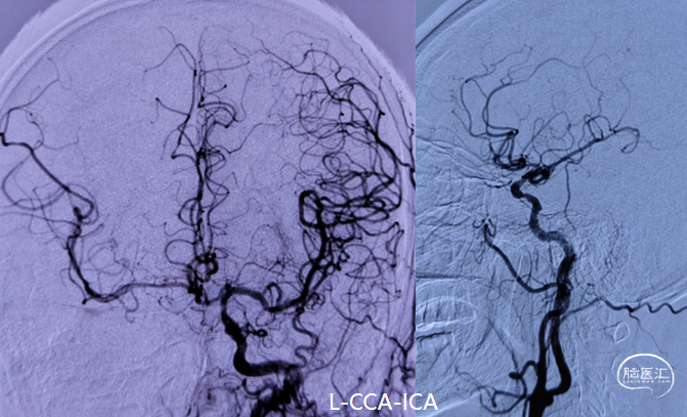

DSA造影(2024.11.07)

右侧后交通动脉开放,右侧颈动脉颅内段浅淡显影。